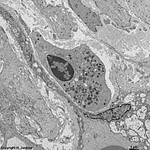

neutrophil in connective

tissue human umbilical cord

detail: cytoplasm with

organelle

Neutrophilic granulocytes (neutrophils, segmented neutrophilic granulocytes; Terminologia histologica: Granulocyti neutrophili, Neutrophili, Granulocyti neutrophili segmentonucleares) belong to the white blood cells (leucocytes; Terminologia histologica: Leucocyti) of which they comprise the majority, i.e. 50 to 75 % in differential blood count. Neutrophils are microphages and thus are capable to incorporate foreign materials via phagocytosis.

Neutrophils are about spherical when circulating in blood, in the connective tissue, however, they appear somewhat longer and ovoid. When cut at maximal diameter they have a width of 9 to 12 maximal 15 µm. Under stimulation plenty of elongated pseudopods form from the cell membrane extending some hundred nanometres. The nuclei of neutrophils are rich in heterochromatin resulting in an intense basophily making it hard to distinguish nucleoli in light microscopy. Due to the considerable variations of nuclear morphology the term polymorph nucleus has been established for neutrophils. Like the other blood cells neutrophils derive from stem cells and progenitor cells of the bone marrow from where they migrate into the blood. After this release the still young neutrophils show bend rod-like nuclei thus the juvenile neutrophils  (neutrophilic metamyelocytes; Terminologia histologica: Metamyelocyti neutrophili, Granulocyti neutrophili juveniles) are also called

segmented neutrophilic granulocytes are cells of diameters of 10 - 15 µm with 3 - 4 nuclear segments interconnected via ~100 nm thin nuclear bridges. In case of too low blood serum levels of vitamin B12 of folic acid a so called hypersegmentation of the nuclei gets evident, i.e. nuclei show 5 or more segments.